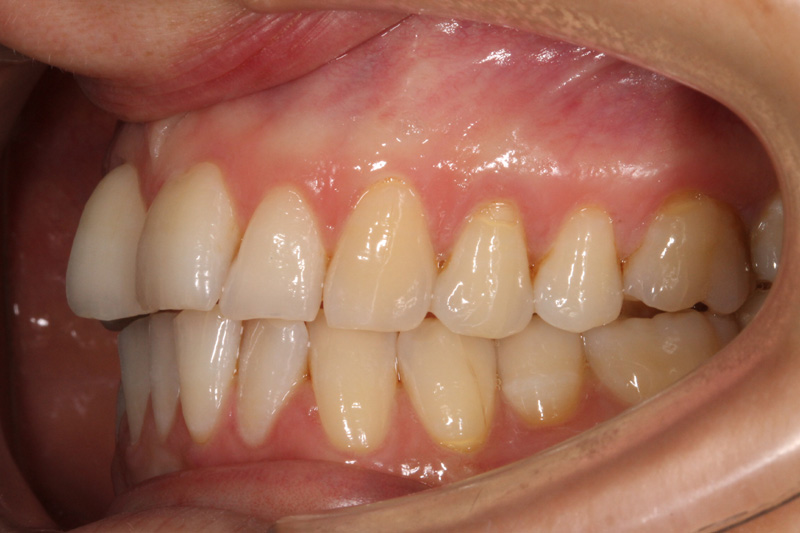

La paziente si presenta alla nostra osservazione con una frattura verticale di un primo premolare superiore.

L'impianto inserito dopo l'estrazione è un Starumann Tapered Effect di 4,1 mm di diametro e 12 mm di lunghezza.

A causa di un gap marginale > di 2 mm viene ritenuto necessario un riempimento con osso sintetico, copertura con una spugna di collageno e sutura con un punto continuo incorciato.